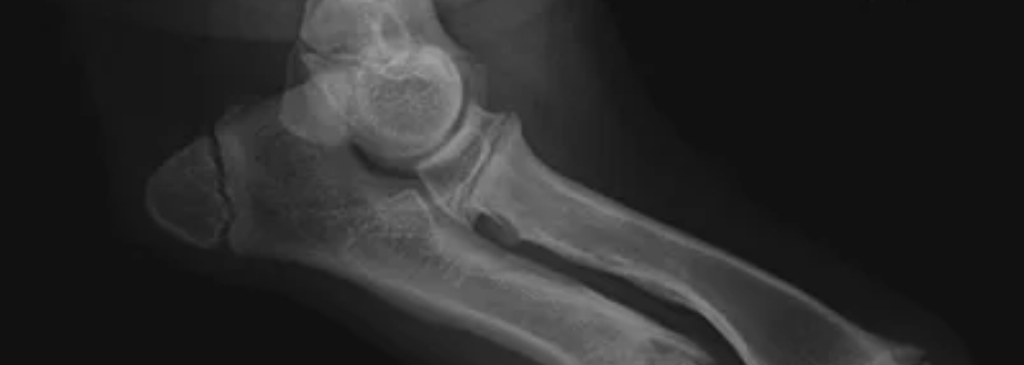

Das Ellbogengelenk

| O | = Oberarm (Humerus) |

| E | = Elle (Ulna) |

| S | = Speiche (Radius) |

| T | = Trochlea Humeri (Gelenkwalze) |

| 1 | = Processus anconaeus |

| 2 | = Epicondylus medialis |

| 3 | = Olekranon |

| 4 | = Processus coronoideus lateralis |

| 5 | = Processus coronoideus medialis |

Auf dem Röntgenbild kann man gut erkennen, wie wichtig es ist, dass die beteiligten 3 Knochen, die das Ellbogengelenk bilden, hundertprozentig übereinstimmen müssen, damit ein gut funktionierendes Gelenk entsteht. Dieses Gelenk muss immerhin fast 80 % vom Körpergewicht des Hundes tragen.

Kommt es nun an den betroffenen Knochen zu Fehlbildungen, verlagert sich die Gewichtsverteilung auf der Gelenkwalze und es kommt zu einer Überbelastung an einer anderen Stelle.

Da die Fehlbildungen an verschiedenen Stellen der Knochen auftreten können, bestimmt der Abschnitt der Fehlbildung das Krankheitsbild. Damit man die verschiedenen Krankheitsbilder versteht, ist es wichtig zu wissen, wie sich das Ellbogengelenk zusammensetzt.

Der Oberarm bildet an seinem Ende die Gelenkwalze, diese teilt man in einen äußeren und inneren Abschnitt ein. Anders als beim Hüftgelenk, wird diese Gelenkwalze nicht in einer Pfanne die aus einem Knochen besteht umschlossen, sondern diese “Pfanne” wird aus 2 Knochen gebildet.

Diese Pfanne setzt sich zusammen aus der Speiche und der Elle. Die Speiche, die mit dem Radiuskopf endet, übernimmt den hauptsächlichen Teil der Stützfunktion der Oberarmgelenkwalze.

Der andere Teil der Pfanne wird aus der Elle gebildet, die mit ihrem Fortsatz die Gelenkwalze umschließt. Dieser Teil der Elle hat eine halbmondförmige Aussparung.